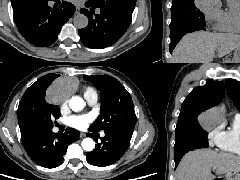

实变是OP病例中最常见的发现,发生在近75%的病例中,病变通常在双基底、支气管血管周围和/或外周(图2,3)。实变可以发生在肺的任何部位,边界清晰或模糊,呈游走性的特点(图4,5),可以呈局灶性,多发性和弥漫性,也可以表现为结节或肿块(图6)。实变常伴支气管充气征,可伴散在的磨玻璃样低密度或小实质结节。以主要的或完全的磨玻璃低密度为表现的较少见(图7)。磨玻璃低密度合并小叶间隔增厚可表现为铺路征(图8)。

图3 支气管血管束分布 在活检证实的机化性肺炎患者中,通过中(A)和下(B)肺区的轴位增强CT扫描图像显示双侧多灶性支气管血管周围实变灶。